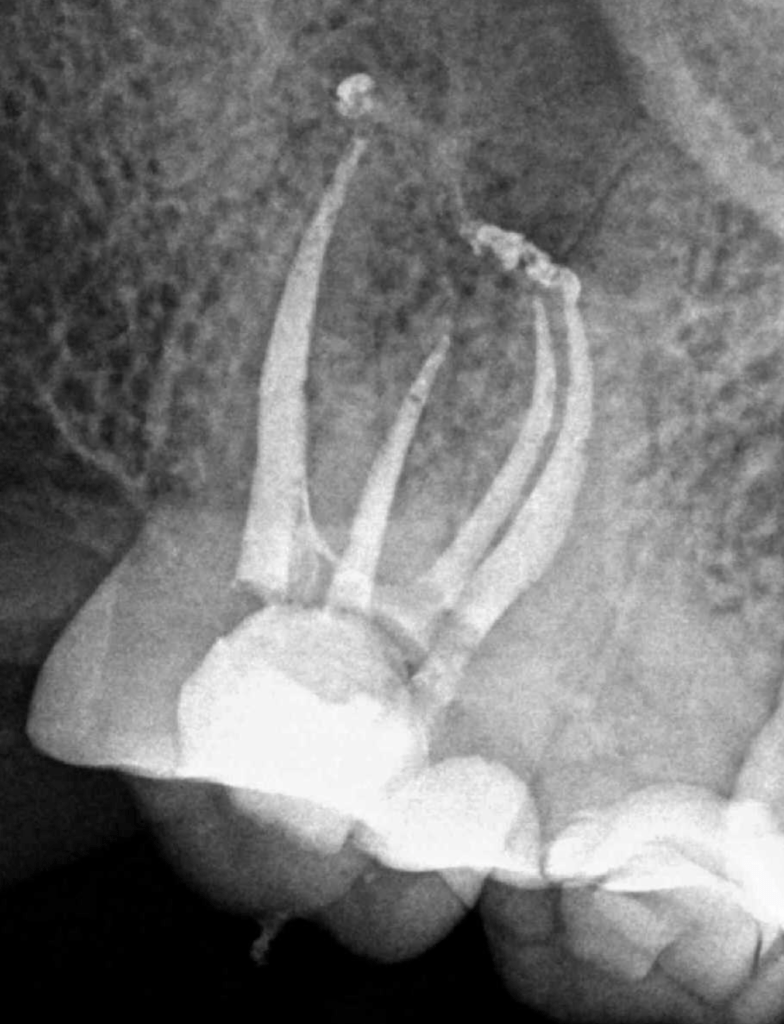

Casos de anatomia compleja

Molar gran curvatura bifurcación palatino